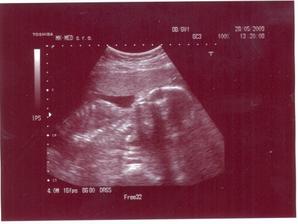

Druhé pokračovanie Filpkovho albumu. Výsledky z glukózových testov vyšli OK. Ďalšia poradňa bude 28.5.2009. Rozmýšľame nad 3D UTZ... V poradni všetko OK. Je to jasný chalanisko 🙂. Ďalšia poradňa bude 25.6.2009. Dnes 2.6.2009 tatinko po prvý raz cítil Filipkov kopanec 🙂))))). HURÁ. 23.6.2009 ideme na predpôrodnú prípravu. V poradni všetko OK. Zmenili nám termín pôrodu na 13.9.2009. Nástup na MD 19.7.2009. 23.7.2009 je krčok skrátený o centimeter. Mali by sme sa skľudniť a viac odpočívať. Filipko má predsa len ešte čas... 5.8.2009 UTZ na Kramároch: Filipko váži cca 2800 gramov. Prietoky OK. Filipko je dole hlavičkou a pretočil sa do I. polohy. No nie je to úžasné dieťatko? Termín pôrodu zmenený na 6.9.2009. Ďalšia poradňa 10.8.2008 taktiež už na Kramároch. 10.8.2009: Krčok je na tom tak ako minule 🙂. 12.8. bol tatinko na príprave pre oteckov na pôrod 🙂. Ďalšia poradňa bude 17.8.2009 (monitor + krv na PEDU). Monitor dopadol dobre. Všetko je v poriadku. Filipko kopal a prevaloval sa v brušku o dušu, takže to bola celkom sranda 🙂. Ďalší UTZ bude 26.8.2009. 22.8.2009 (37+6) sa mi objavila linea nigra. Asi je to rarita, že sa objaví na konci tehotenstva ... 26.8.2009- UTZ- Filipko váži 3300 gramov 🙂). Všetko je pripravené na konečnú fázu tehotenstva. Teraz budeme chodiť ukazovať "krk" každý druhý resp. každý deň, aby sa vystihol naj deň D pre maminku aj pre Filipka. Ďalšia poradňa bude 28.8.2009, kde uvidíme ako sa otvára "krk"... 28.8.2009- Krk je zatvorený a skrátený na 0,5 cm. Všetko OK. Ďalšia poradňa bude 4.9.2009. V poradni všetko OK. Všetko je zatvorené, takže cez víkend vraj nič nehrozí... V pondelok 7.9.2009 ďalšia kontrola. 7.9.2009 je všetko je po starom. Krk je stále zatvorený ☹((. Ak sa do stredy neotvorí, v piatok nastupujem do nemocnice ☹(. OTVOR SA TY KRČISKO JEDEN !!! Hlavné je, že Filipkovi je stále u maminky v brušku dobre 🙂)))). 9.9.2009: Krk sa strašne málo polepšil ale aj tak zajtra nastupujem do nemocky a budú pôrod vyvolávať. Ak nezaberie, v piatok sa to zopakuje. 19.9:2009: Tak sme konečne doma 🙂. Filipka sa snažili dostať z bruška vyvolávačkou vo štvrtok a tak isto v piatok ale neúspešne. V sobotu a v nedeľu nechali maminku načerpať trochu síl na pondelok. V pondelok 14.9.2009 o 13:00 sa Filipko narodil cisárskym rezom. Filipko pri narodení meral 51 cm a vážil 3320 g. Je zdravučý a krásnučký. Rodičia sú stráááááááášne šťastní.